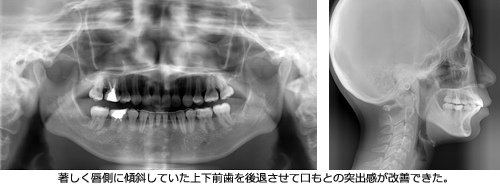

そして、A子さんの承諾のうえで抜歯を行った後、一般的な矯正歯科治療で用いるマルチブラケット(ブレース)をつけた治療を3年6か月行いました。その結果、咬み合わせのバランスが整い、もたついていた口もとの印象もすっきりと変化しました。

●矯正歯科での治療後

●矯正歯科での治療後に行った頭部X線規格写真検査

マルチブラケット治療の前と後を比べてみると、その差は一目瞭然です。